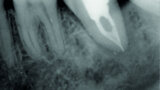

Fig. 3: Pre-op periapical radiograph.